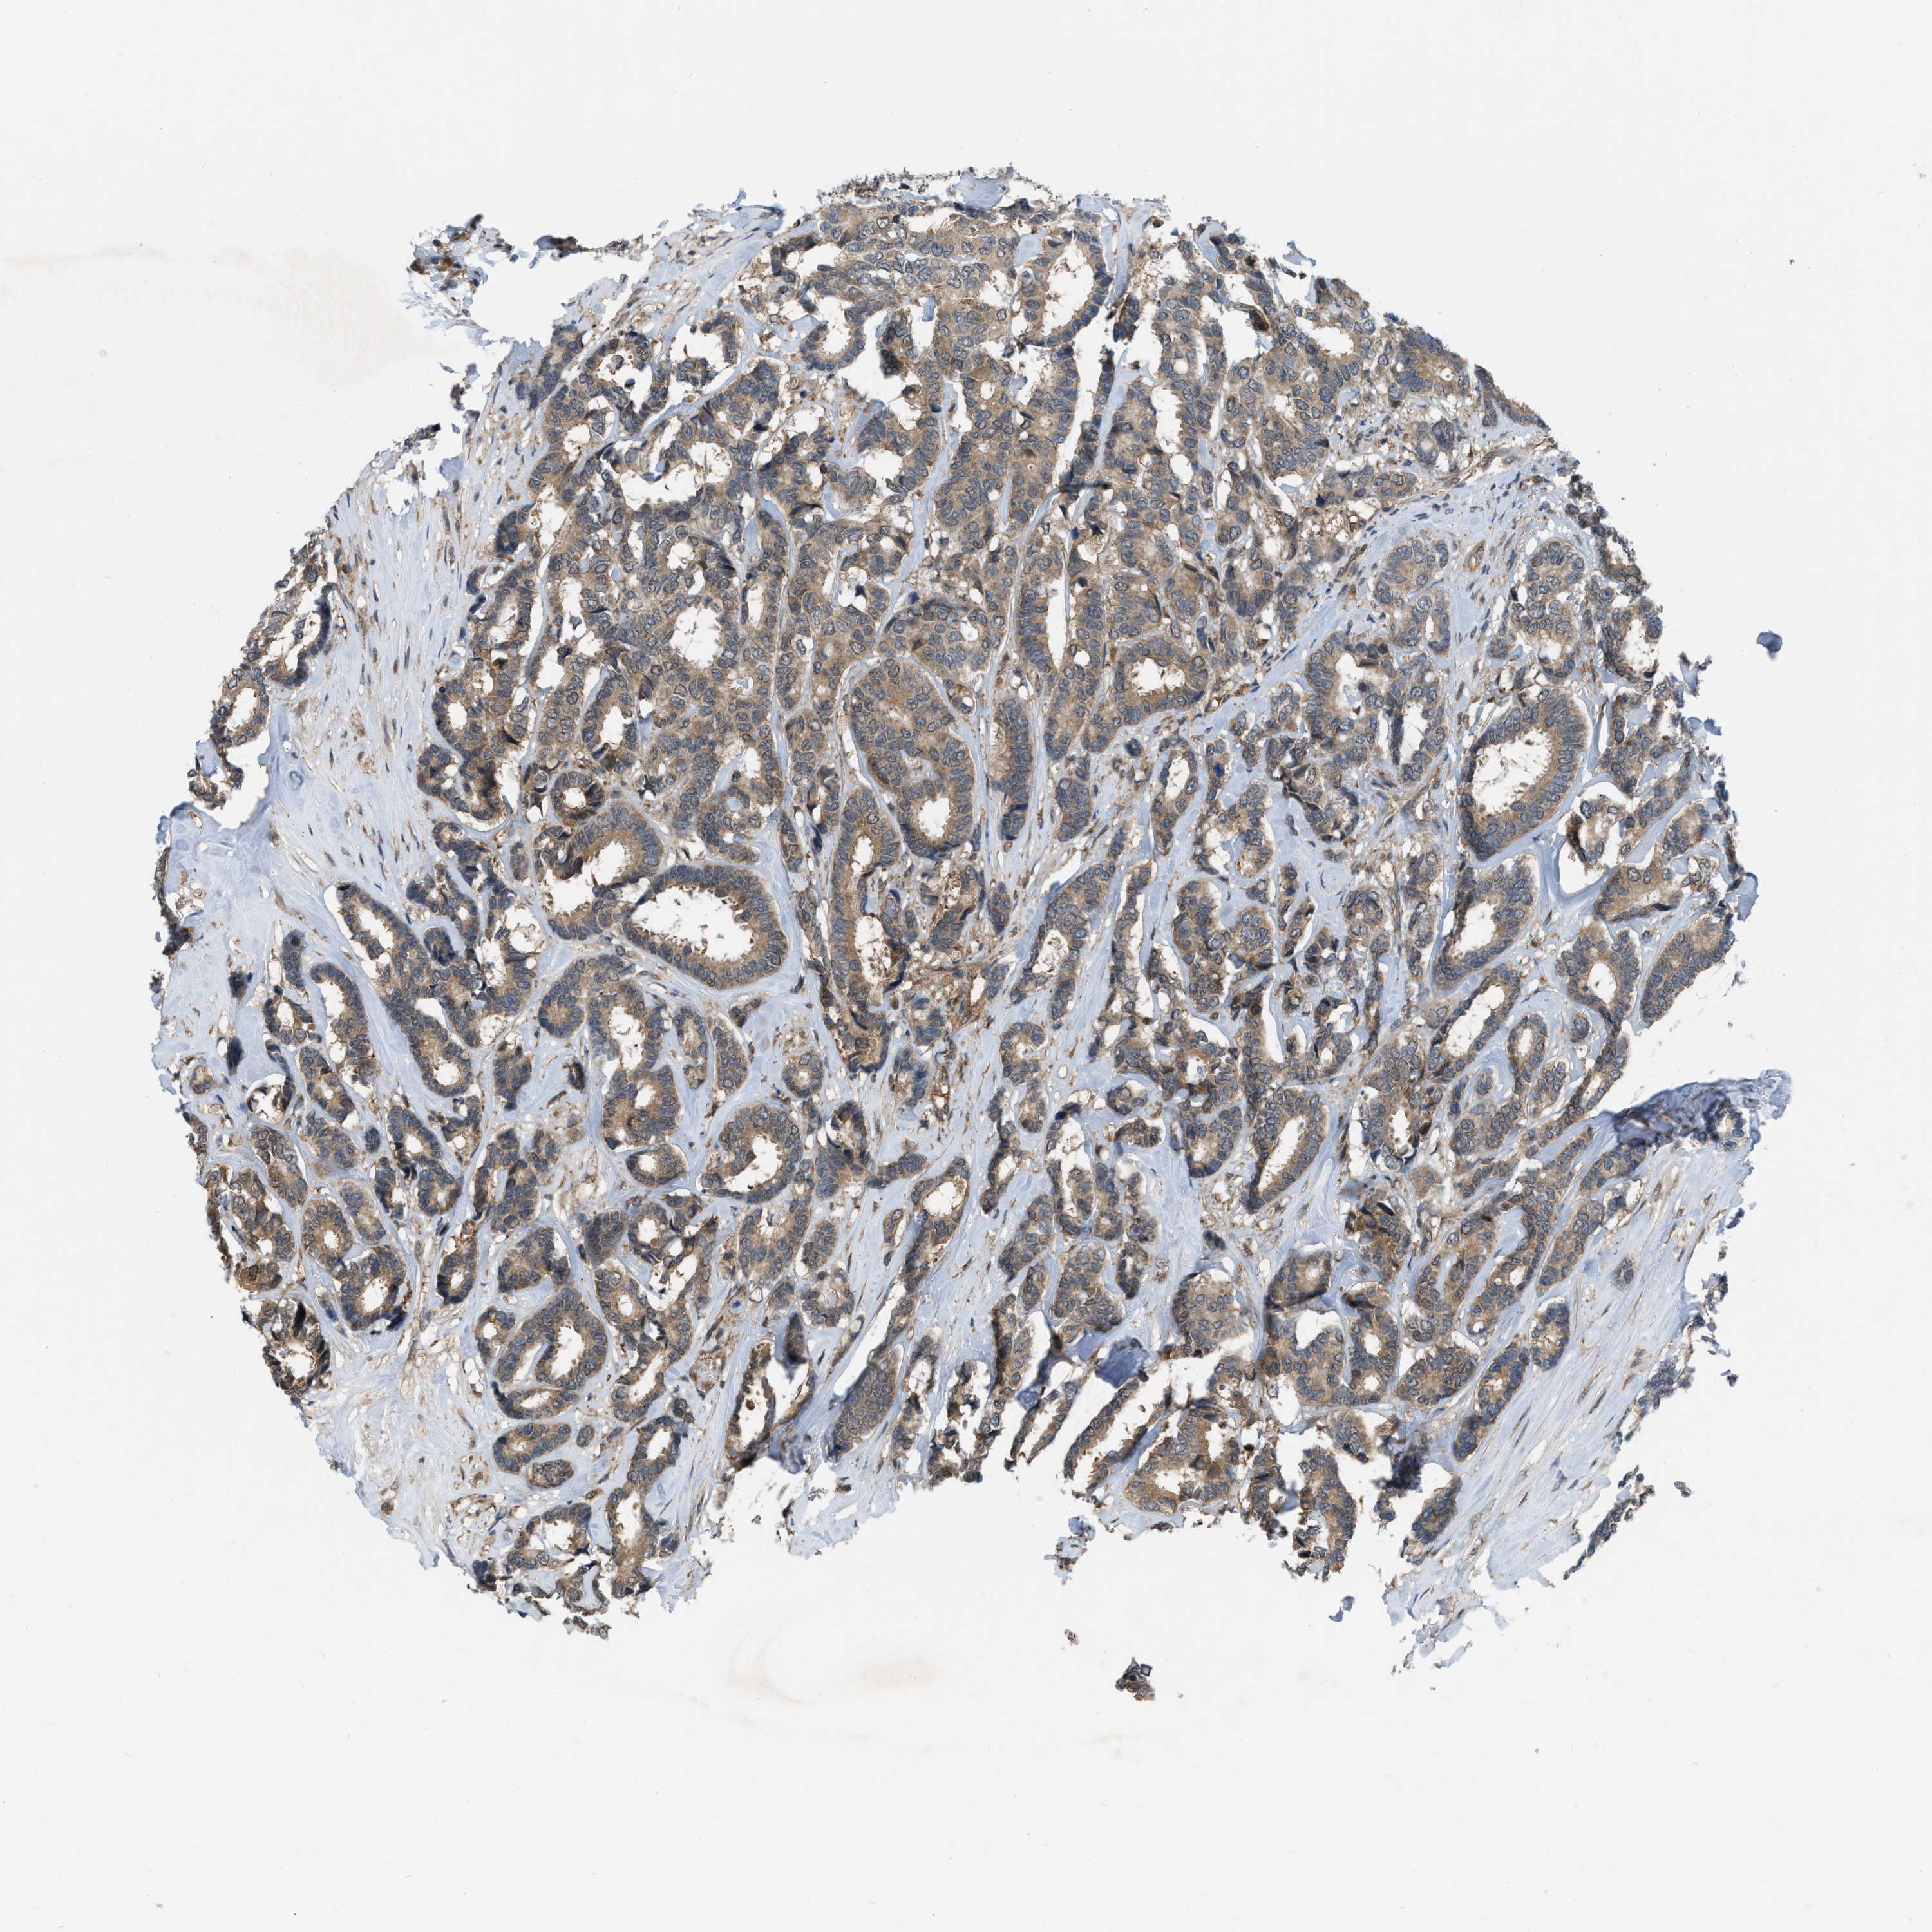

BRCA TCGA BRCA VALIDATION PROTEIN EXPRESSION